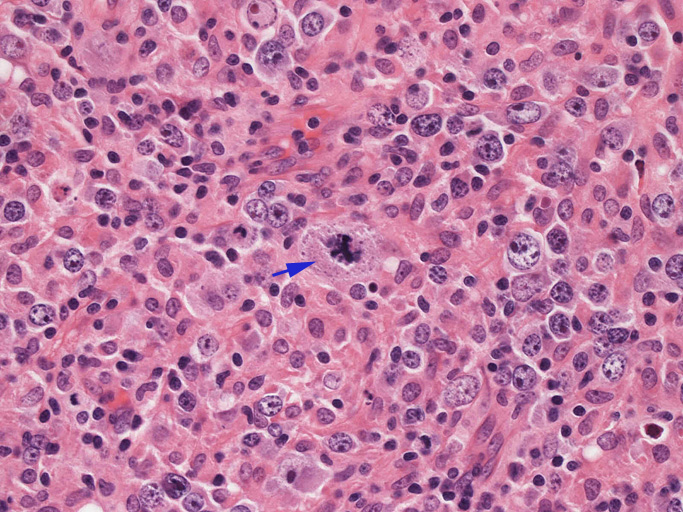

結節構造内では, 好酸性細胞質をもつ組織球の増生を背景に大型異型細胞が散在性または集蔟して増殖している。被膜下にも線維化組織内にbizzarreな大型細胞が認められる。リンパ球は小型リンパ球が大型異型細胞を含む組織球性の結節辺縁に存在する。大型細胞は, centroblastic cellが多く, その他 Hodgkin cell-like cell, RS細胞様巨細胞, 腎臓型の核をもった細胞, 多型核の細胞など多彩な形態を示す。異型核分裂像をふくむ核分裂像が多い。

大型異型細胞の形態